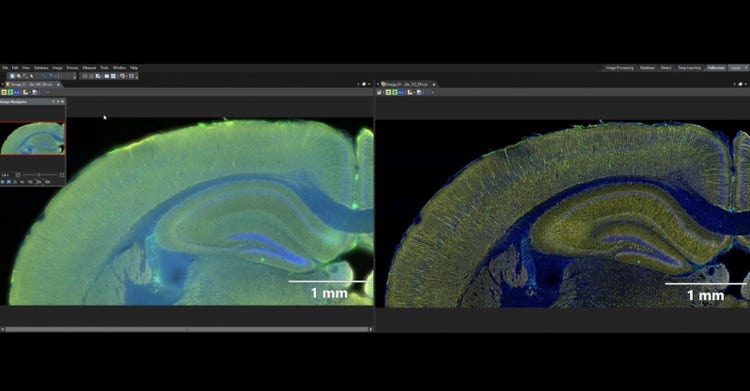

True Clarity in Thick Samples

Capture sharp images in applications where conventional widefield slide scanners lose detail.  The speckle illumination acquisition (VS-SILA) device enables high-quality images of thick samples by removing out-of-focus light through optical sectioning.

VS-SILA

The VS-SILA (speckle illumination acquisition) optical sectioning device easily integrates into your VS200 system and software. Speckles are used to obtain high-contrast images, removing out-of-focus light to deliver sharp images, especially from thick samples. The image is computed during the scan, and there’s no need for post-processing, so the device has a minimal impact on acquisition speed.